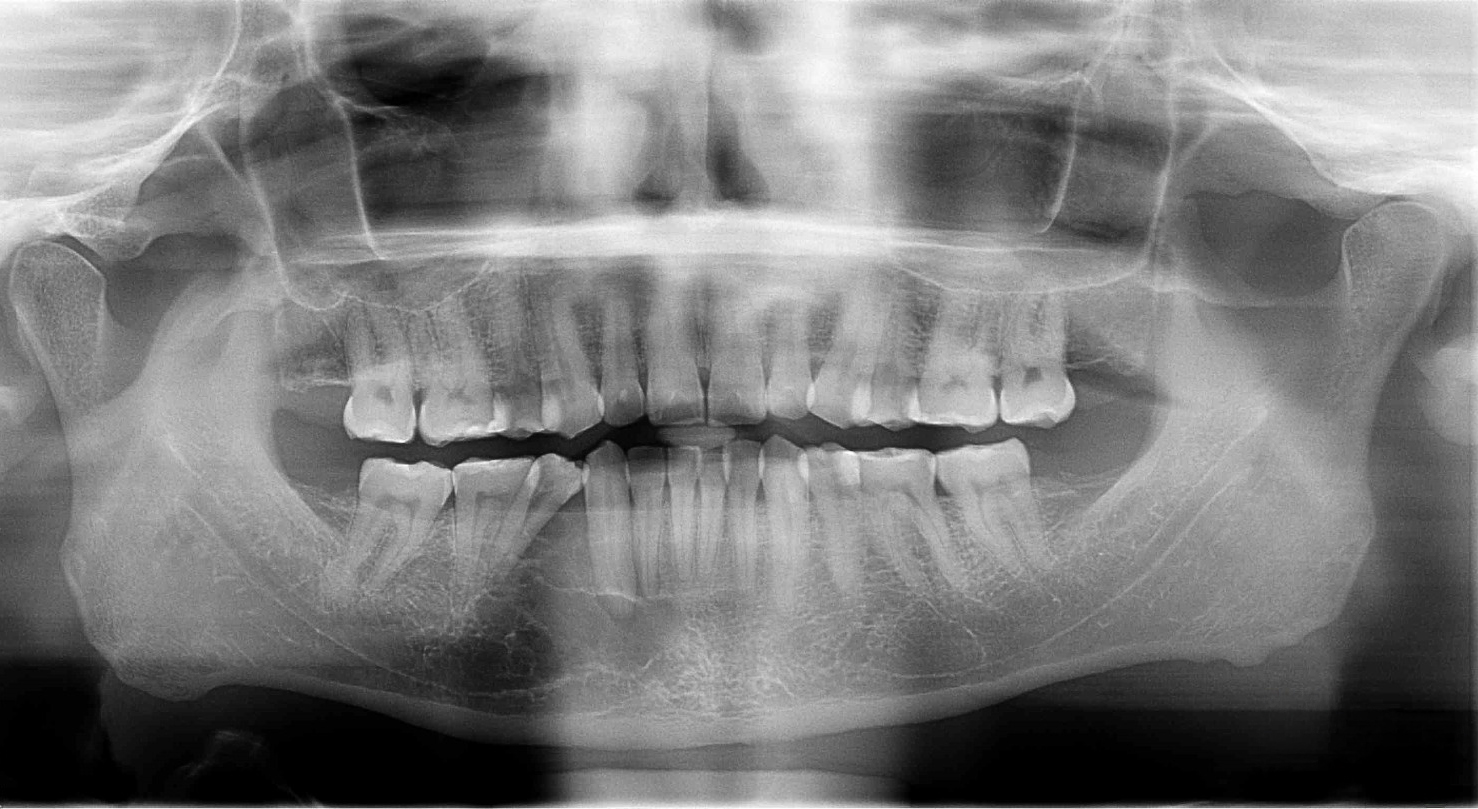

Initial X-ray Showed Odontogenic Myxoma of the Right MandibleAfter examinations, he received a diagnosis that sounded scary at first. It was an odontogenic myxoma of the right mandible. This is a rare tumor that grows inside the jawbone and can slowly destroy bone tissue. Peter understood that this was not a case for delays or half-measures. He wanted a top specialist and a clinic that handles complex maxillofacial surgery on a high level.

CT Scan Before the SurgeryWhen Peter arrived in Munich, the admission examination was calm and structured. The clinical examination revealed no visible pathology. But the most important answers came from three-dimensional imaging (DVT). The scan revealed a lytic, multi-chambered change in the right lower jaw. It was affecting the area around the root tips, and teeth 42, 43, and 44 were involved in the osteolytic process.